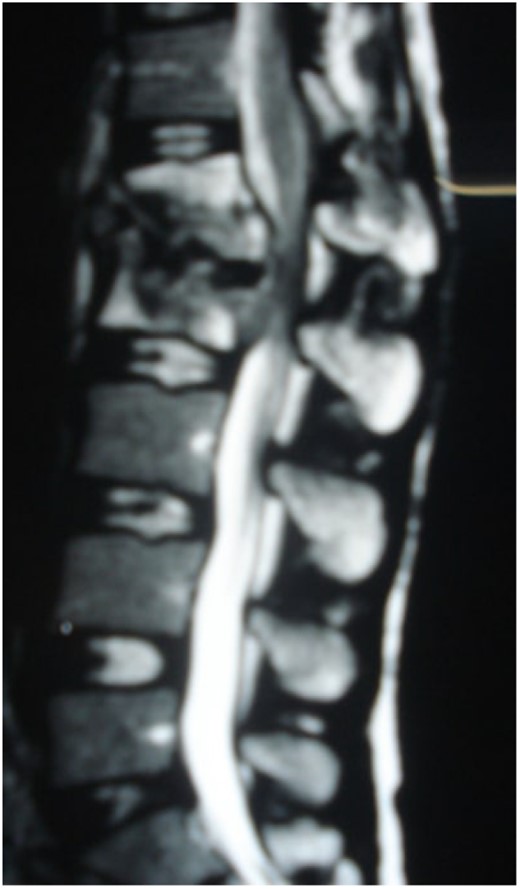

A 24-year-old farmer female was admitted to the Department of Neurosurgery with low back pain, no fever, cough, motor deficit, or any symptoms. Medical, surgical, family histories and physical examinations were unremarkable. The laboratory findings showed a white cell count of 9.8 × 103/μL, C-reactive protein concentrations of 20, erythrocyte sedimentation rate of 50 mm/1 h, 90 mm/2 h and tuberculin skin test was positive. X-ray films showed the collapse of the L1, L2 vertebrae, and L1–2 intervertebral space (Fig. 1). An abscess was observed at the L1–L2 vertebral level in lumbar magnetic resonance imaging (MRI) (Fig. 2). Chest X-rays and Sputum smear were negative. The patient was treated with anti-TB treatment (Isoniazid, Rifampicin, Ethambutol, Pyrazinamide) due to spinal TB findings on MRI (Fig. 3). After 40 days, the patient was diagnosed with grade 1/5 lower limb weakness, and bladder and bowel dysfunction, with no impairment in sensation, which predicts spinal infection. MRI confirmed these abnormalities and showed typical findings such as vertebral endplate destruction, bone marrow and disk signal abnormalities, and paravertebral or epidural abscesses (Fig. 3). Due to clinical manifestations and MRI spinal TB findings (Fig. 3), the patient underwent surgical debridement, interbody fusion and internal fixation with fibular autografting and supplemental posterior spinal stabilisation using a posterior-only approach. On post-operative follow-up, the treatment continued for 9 months, in addition to physical therapy for lower limb weakness. In the end, the patient returned to full motion with grade 5/5 in the lower limb, normal sensation, and no bladder or bowel incontinence. No recurrence was observed in the grafting area. Radiologically 2, 6 and 12 months, 14 years’ post-operation, the patient had achieved full bony graft spinal fusion (Figs 4–6).

Sagittal T2-weighted MRI shows severe disco vertebral destruction, the formation of epidural abscess and compression of the spinal cord at the L1–2 level.

Lumbar T1 and T2 consistent with an abscess at the L1–2 vertebral level. (A) and (B) showed that the height of the L1 and L2 vertebral bodies was markedly reduced and the dural sac and spinal cord were severely compressed by an abscess posterior to the vertebral body. (C and D) Axial T1 shows a well-defined paraspinal abscess. The anterior epidural abscess compresses the spinal cord.